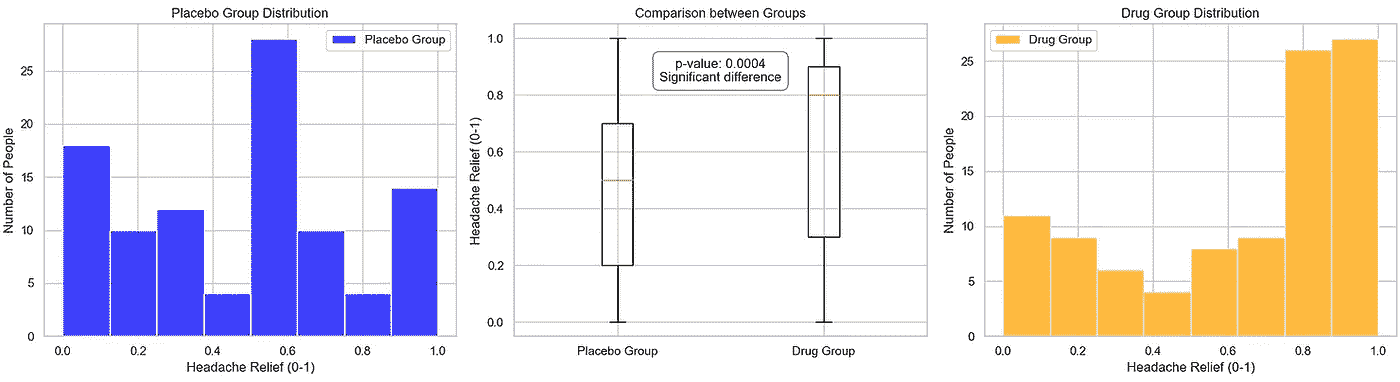

情景 2:极端/非常小的 p 值,观察结果与预期结果之间的显著差异

为了模拟第二种情景,我们对药物组的数值引入了 1 的偏倚,注意到这种操作在真实的临床试验中非常值得怀疑,可能产生深远的影响。我们再次将数据输入到我们的 pvalue_significance_estimator 函数中。

np.random.seed(123)

placebo_group = [round(random.uniform(0, 1), 1) for _ in range(100)] # Placebo group data

drug_group = [round(random.uniform(0, 1), 1) for _ in range(100)] # Drug group data

bias_percentage = 40 # Percentage of values to bias towards 1

bias_factor = 0.75

drug_group = [

round(value * (1 - bias_factor) + bias_factor, 1)

if random.uniform(0, 100) <= bias_percentage

else value

for value in drug_group

]

pvalue_significance_estimator(placebo_group, drug_group)

图片来源:作者

在这里,我们可以看到两个组均值的显著差异,以及一个非常小的 p 值。这表明药物确实有影响。尽管这种简化分析仅比较了两个组的均值,且数据直接,但即使在这种情况下,指向药物有效性的备择假设仍需进一步研究。